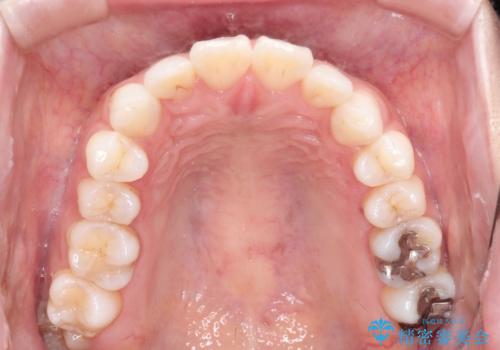

- 口が閉じずらく、口元が出ていることを主訴に来院されました。

上下左右の歯を1本ずつ抜歯して、そのスペースを利用して口元を引っ込める計画としました。